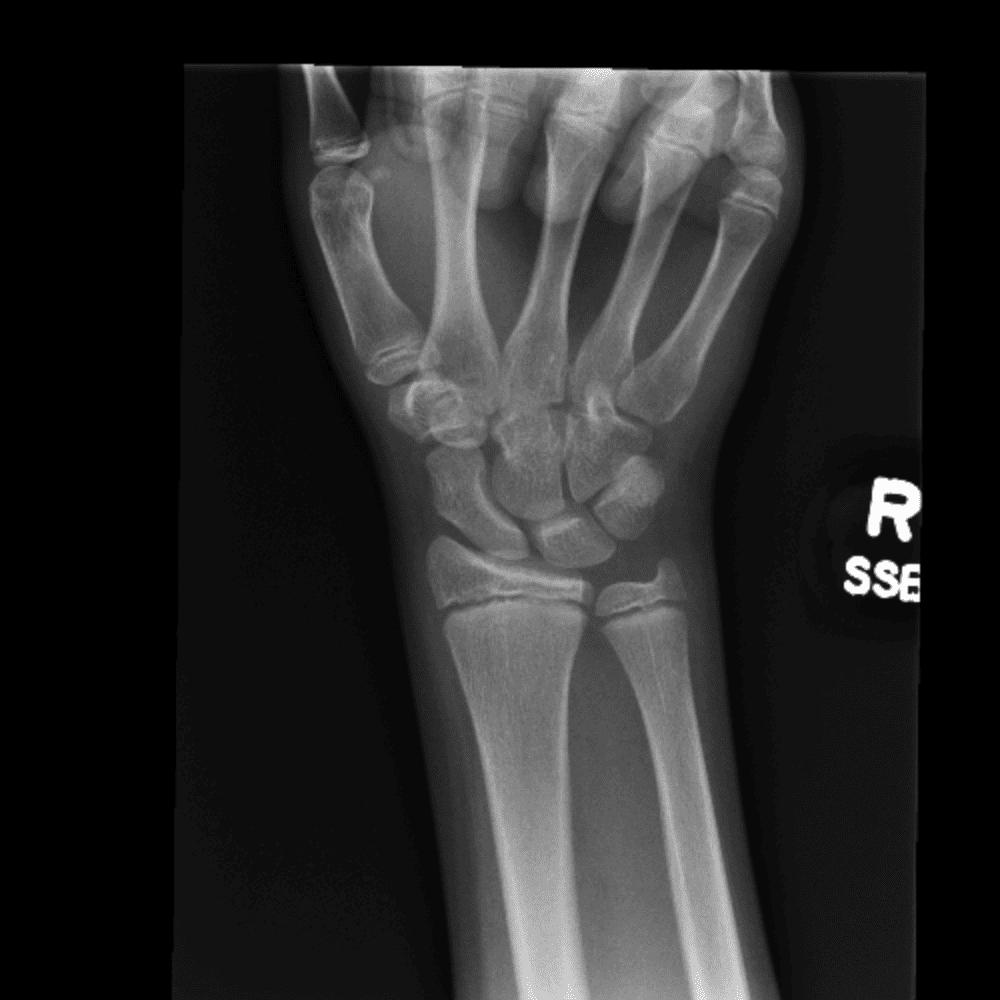

Simulates call by including subtle or difficult cases and some normals.

30 cases